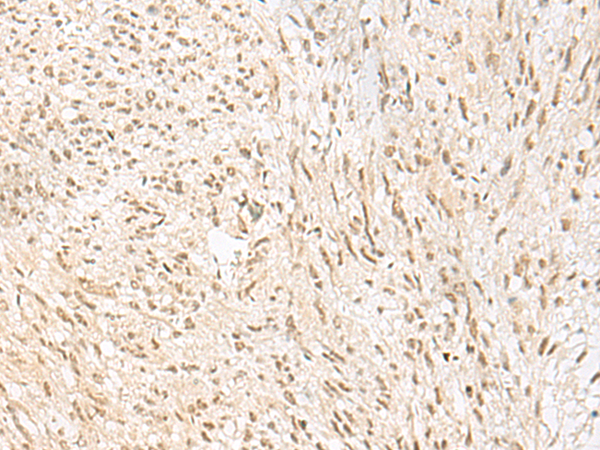

分类: 科研抗体货号: P09903别名: CTLH; GID2; RMD5; GID2A; p44CTLH应用: IHC反应种属: Human, Mouse